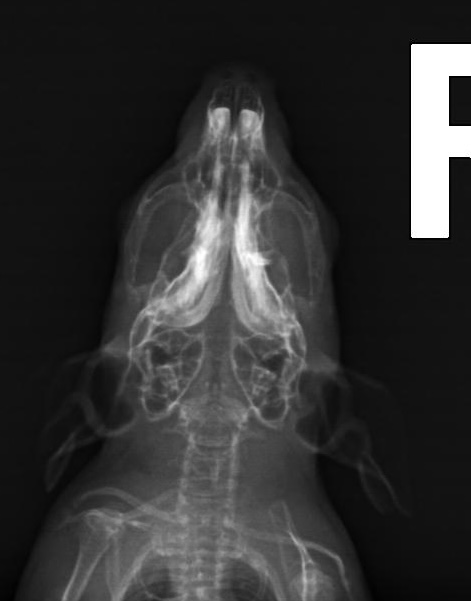

heute gab es doch ein Kontrollröntgen.

Gerade weil es vor Weihnachten super stressig ist, hab ich gesagt sie sollens nur machen, wenns zeitlich rein passt. Und hat es wohl

Hier könnt ihr mit gucken:

Der Unterschied zwischen diesen und den ersten Bildern beträgt übrigens 2 Monate (und ein Tag)

Wow, ohne davon wirklich Ahnung zu haben, sieht man auf den beiden Fotos von oben geröntgt sehr deutlich die positive Entwicklung